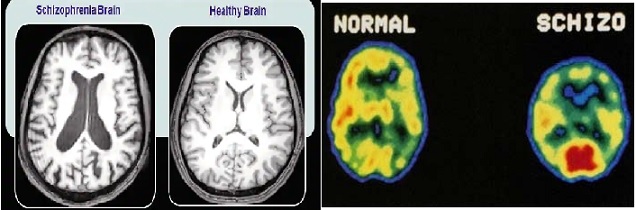

Manifestações de paranóia/esquizofrenia (40) - É como viver num metaverso